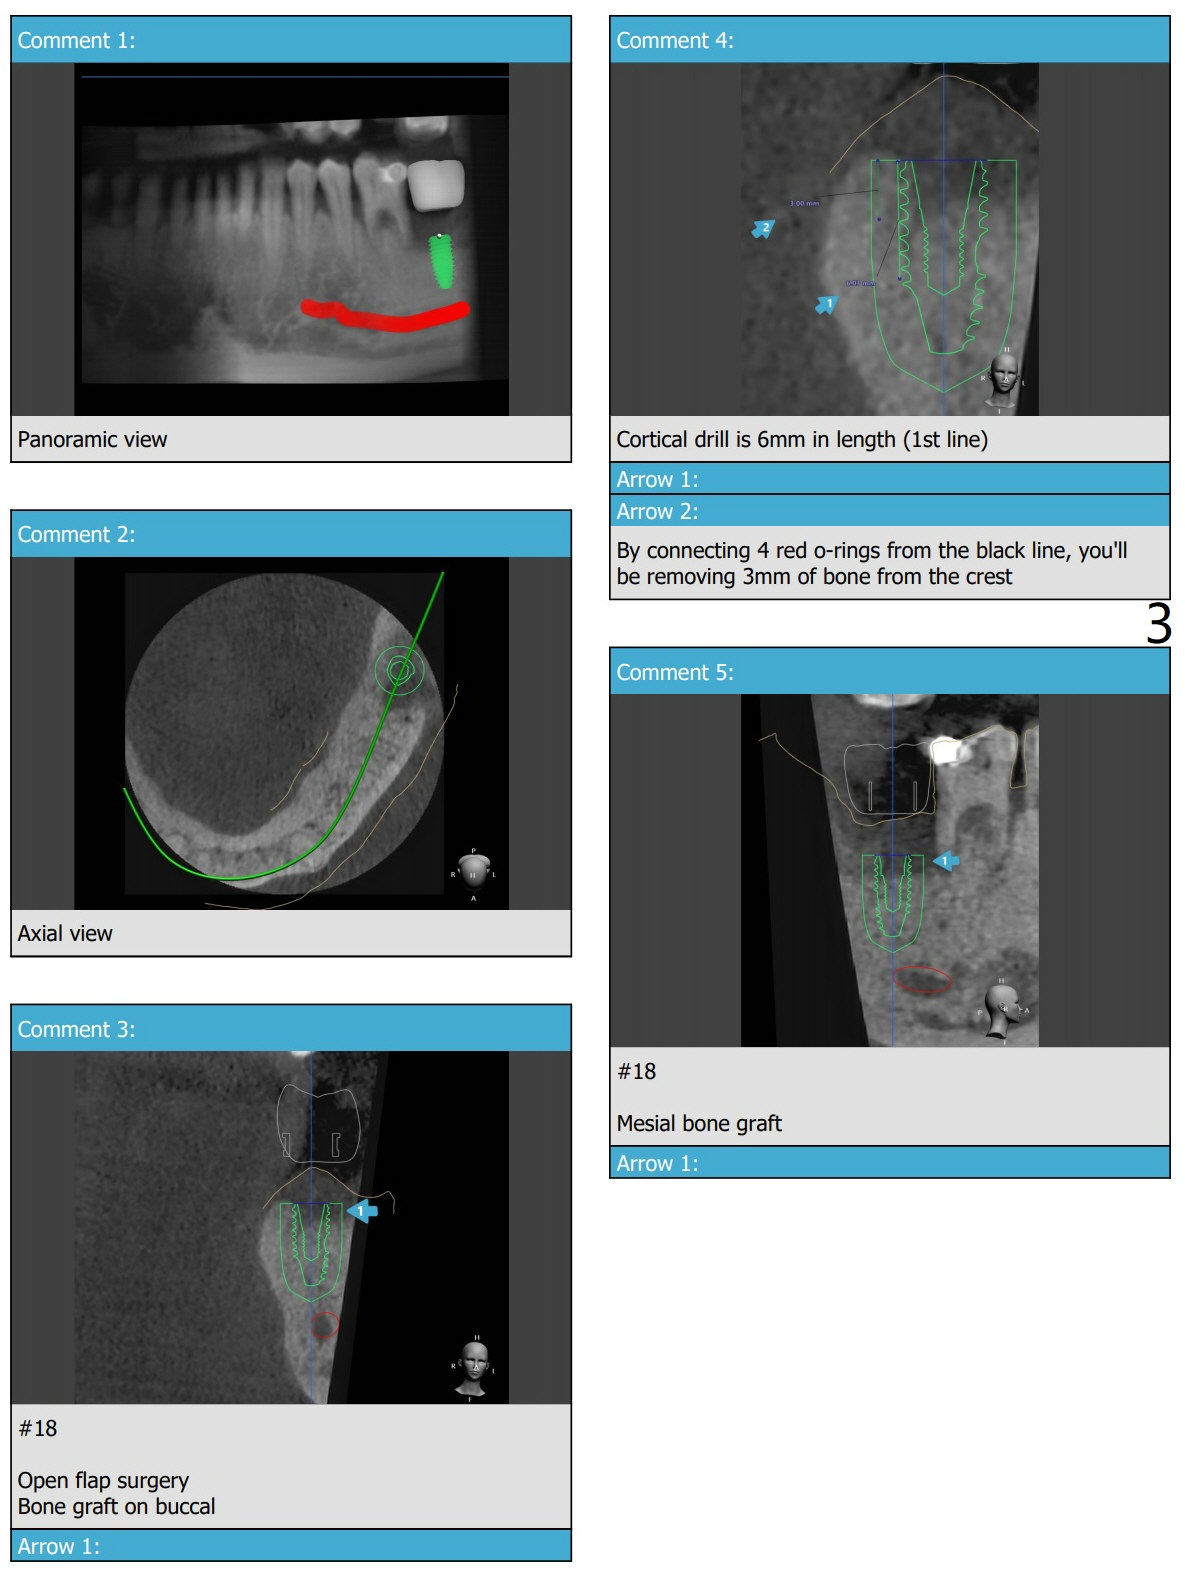

18号牙远中牙槽窝植骨术后5个月,病人回来植牙。由于近中骨质吸收严重,植体植入表浅,需要再次植骨。植骨范围大(颊侧,近中)以及19远中,需要粘性骨粉以及PRF膜x2